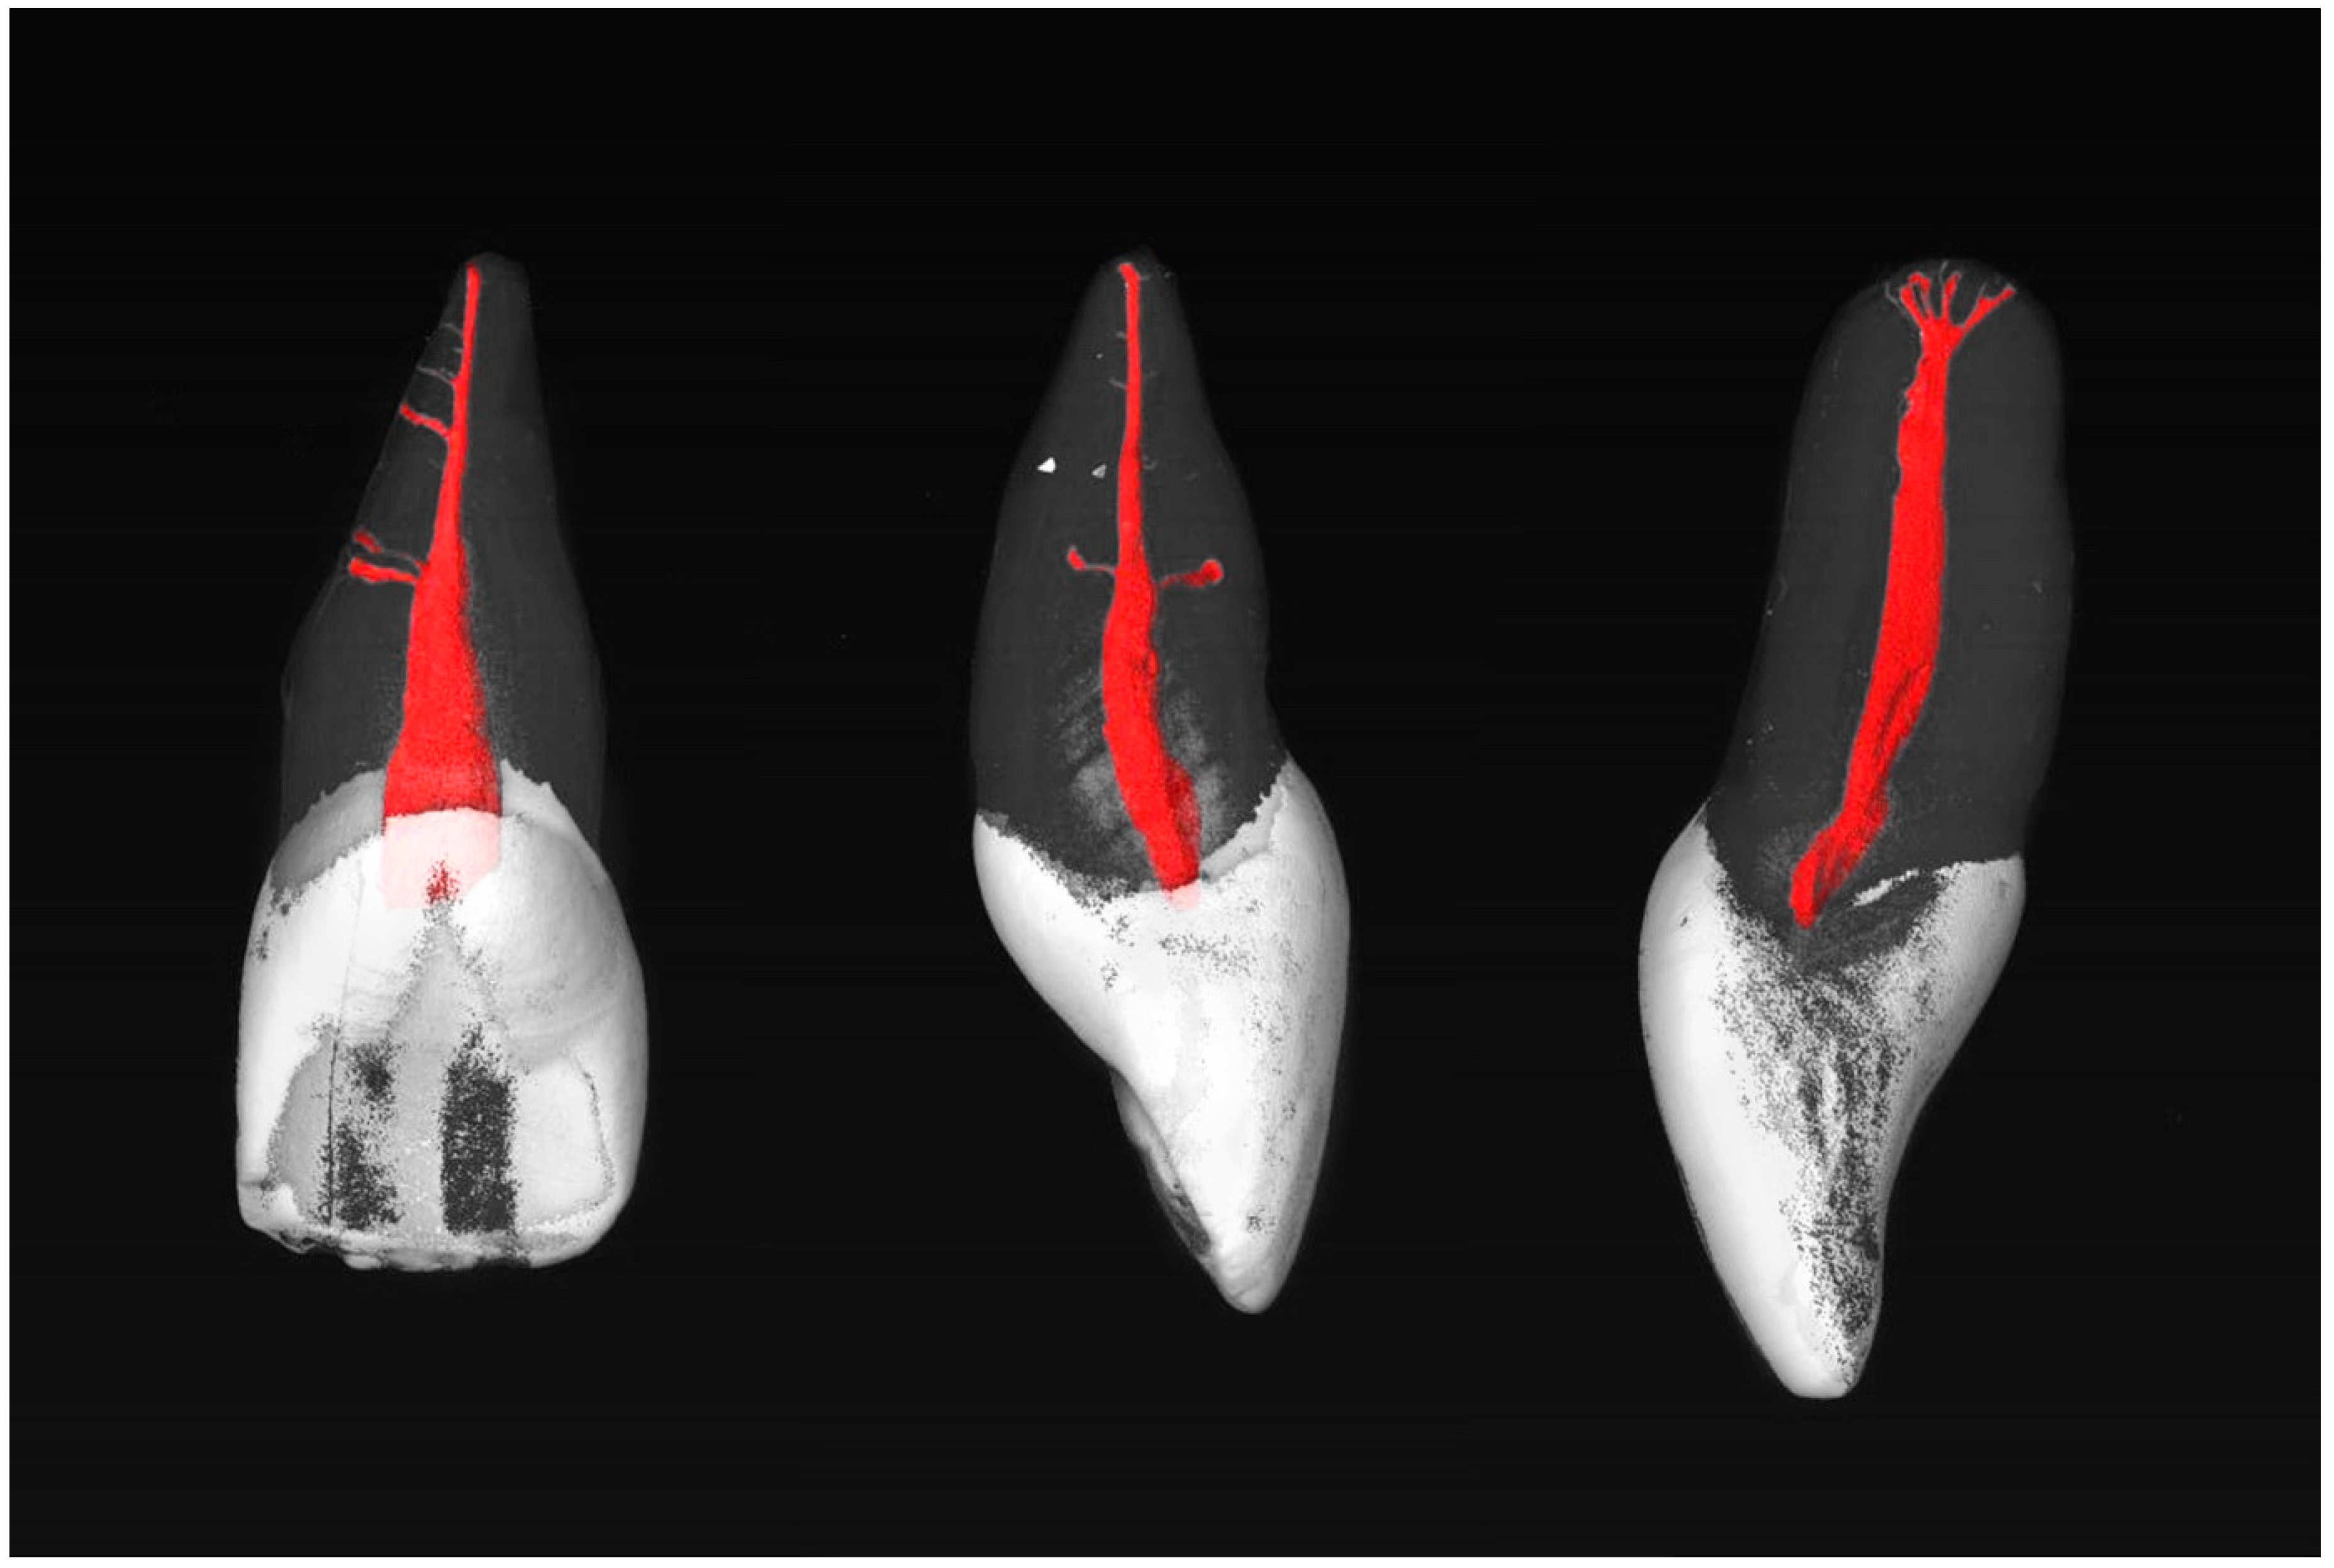

Most commonly, the MxCIs had no accessory apical foramina (85.7%). One (8.0%), two (3.6%), three (0.9%), or four (1.8%) could be observed (diameter > 0.1 mm). Examples of the MxCI specimens are shown in Figure 1 and Figure 2.

Figure 2.

µCT images of maxillary central incisors with an RCC of 1-1-1/1 with four accessory foramina, including two accessory canals in the middle and apical thirds of the root (left), two accessory canals in the middle third of the root (center), and three accessory foramina in the apical root third (right).